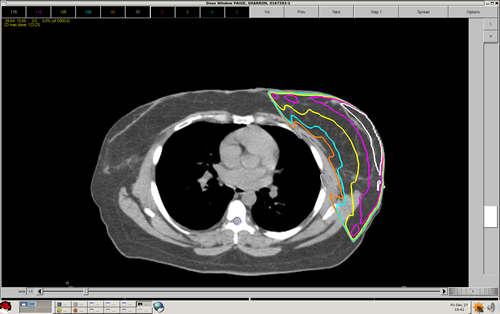

Quiz: Question 4

When adding a wedge (or wedges) to a typical breast cancer treatment plan, the orientation of the wedge(s) is: a) Heel to posterior/medial – toward the thickest part of the breast b) Heel anterior/lateral – toward the nipple of the breast c) Heel superior – toward the head of the patient d) Heel inferior – toward the feet of the patient